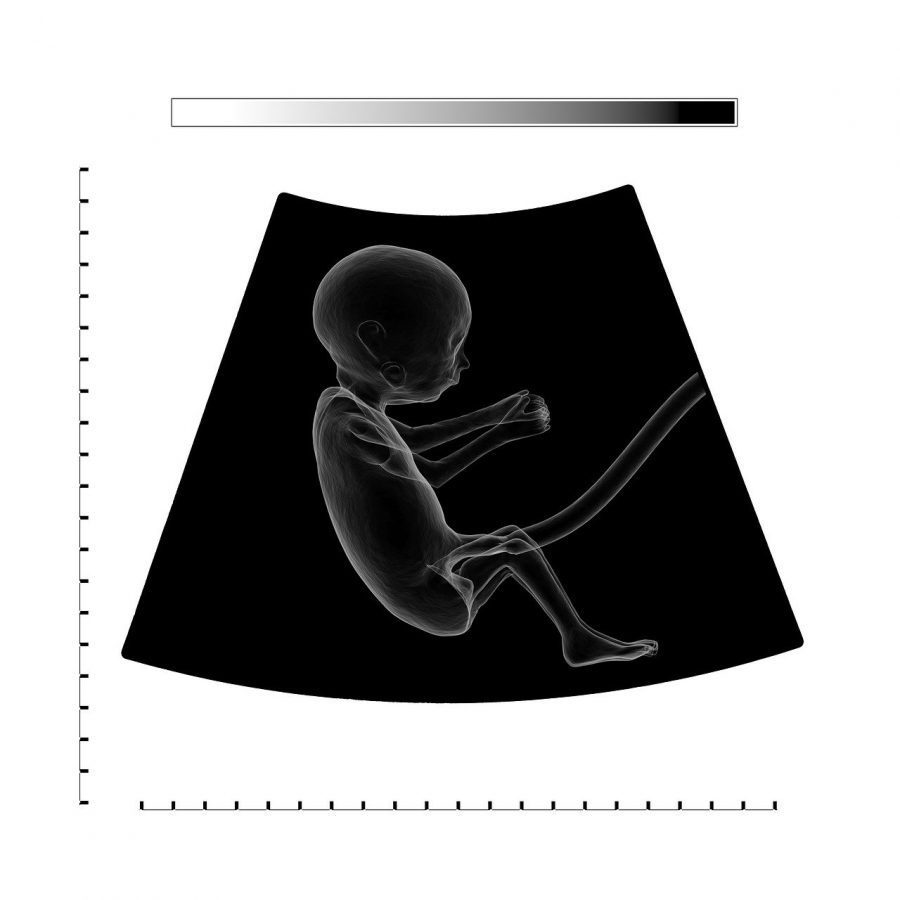

Il liquido amniotico è un liquido protettivo che circonda il bambino durante la gravidanza e lo protegge da urti e movimenti improvvisi. Il liquido è contenuto nel sacco amniotico e fornisce gli anticorpi, i nutrienti e gli ormoni necessari allo sviluppo del feto.

Inoltre, è responsabile della sicurezza e dell’aiuto del bambino:

- I bambini si muovono in modo sicuro nel grembo materno (il che porta a una crescita ossea e a uno sviluppo muscolare adeguati)

- Aiuta i polmoni a svilupparsi correttamente

- Fornisce una temperatura costante al bambino

- Evita la pressione sul cordone ombelicale